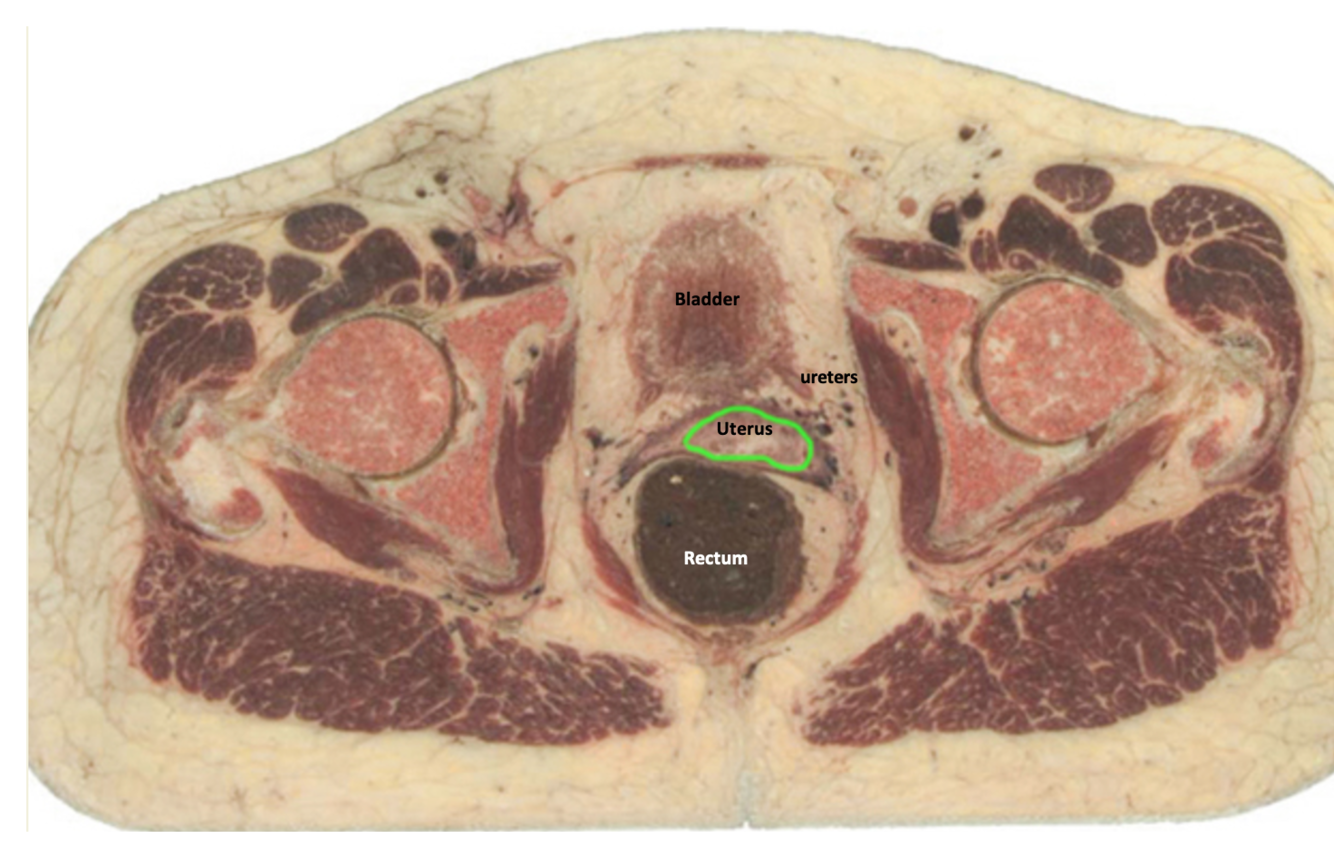

Name the vesicles (blue) and structure (green)